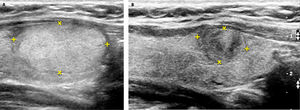

Nódulos tiroideos.

A: A la izquierda un nódulo tiroideo sólido, isoecogénico (igual ecogenicidad que el resto del lóbulo) y a la derecha la imagen de un nódulo hipoecogénico (más oscuro que el resto del tejido tiroideo normal circundante), en este caso con algunas calcificaciones gruesas (imágenes blancas de ubicación excéntrica, superiores derechas).

B: Corte ecográfico longitudinal de un nódulo tiroideo (entre las cruces): sólido, hiperecogénico, bien delimitado, sin calcificaciones.

C: Nódulo tiroideo quístico (anecogénico): el ultrasonido traspasa la estructura líquida sin generar ecos e inmediatamente dorsal al quiste hay un refuerzo del ultrasonido, por mayor disponibilidad de energía para emitir más ecos.

D: Nódulo tiroideo sólido quístico (o mixto), rodeado por un halo hipoecogénico. La porción periférica del nódulo es sólida, isoecogénica y el centro es líquido (anecogénico).